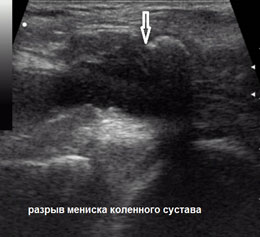

Для исключения повреждения костных структур проводят рентгеновские снимки. Разрывы мениска на снимках не видны, так как мениски прозрачны для рентгеновских лучей. Полностью установить диагноз помогают рентгеновские снимки с контрастированием сустава, ультразвуковое исследование, но более современными методами служат магниторезонансная томография или эндоскопическая артроскопия (осмотр внутренней поверхности сустава при помощи артроскопа).

uzi-diagnostika-УЗИ.jpg  mrt-diagnostika-МРТ.jpg

Полный разрыв заднего рога медиального мениска. УЗИ Полный разрыв заднего рога медиального мениска. МРТ